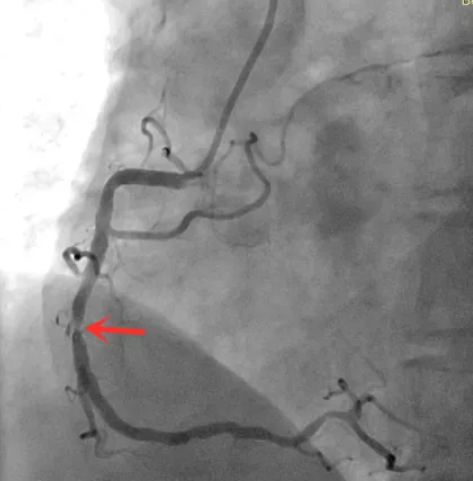

图 | 造影显示:右冠状动脉中段狭窄80-90%